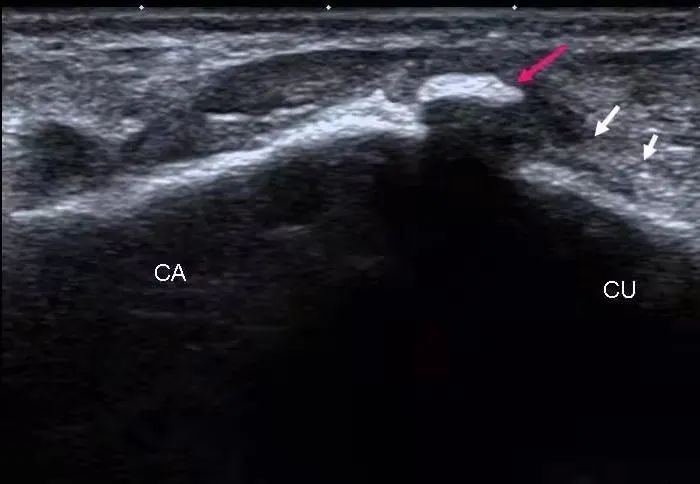

超声显示:尺神经于肘管近端及远端增粗,符合肘管综合征(尺骨骨赘形成,压迫尺神经)